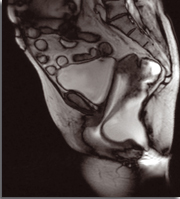

En revanche, hormis le cas particulier des manœuvres endovaginales plus souvent rapportées en cas de rectocèle (Illustration), le type de manœuvres n’avait pas de valeur d’orientation diagnostique (figure).

Manœuvres digitales défécatoires en fonction de la cause